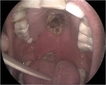

Hamilelik süreci, kadınların fiziksel ve duygusal sağlıkları üzerinde önemli etkiler yaratabilen karmaşık bir dönemdir. Bu dönemde, bazı kadınlar çeşitli sağlık sorunları ile karşılaşabilir. Bu makalede, hamilelikte damak yarası (yarık damak) tedavisinin önemi, nedenleri ve tedavi yöntemleri ele alınacaktır. Damak Yarası Nedir?Damak yarası, doğuştan gelen bir durumdur ve genellikle fetal gelişim sırasında damak bölgesinde meydana gelen anormalliklerden kaynaklanır. Bu durum, damak yapısının tam olarak gelişmemesi nedeniyle ortaya çıkar ve genellikle üst damağın ortasında bir yarık şeklinde görülür. Hamilelikte Damak Yarası NedenleriDamak yarasının oluşumunda çeşitli faktörler etkili olabilir. Bu faktörler arasında genetik, çevresel ve beslenme ile ilgili unsurlar yer almaktadır.

Hamilelikte Damak Yarası BelirtileriDamak yarası, doğumdan önce belirti vermeyebilir. Ancak doğum sonrası bebekte görülen bazı belirtiler, bu durumun varlığını gösterebilir.

Damak Yarası Tedavi YöntemleriDamak yarasının tedavisi genellikle multidisipliner bir yaklaşım gerektirir. Aşağıda tedavi yöntemleri sıralanmıştır: